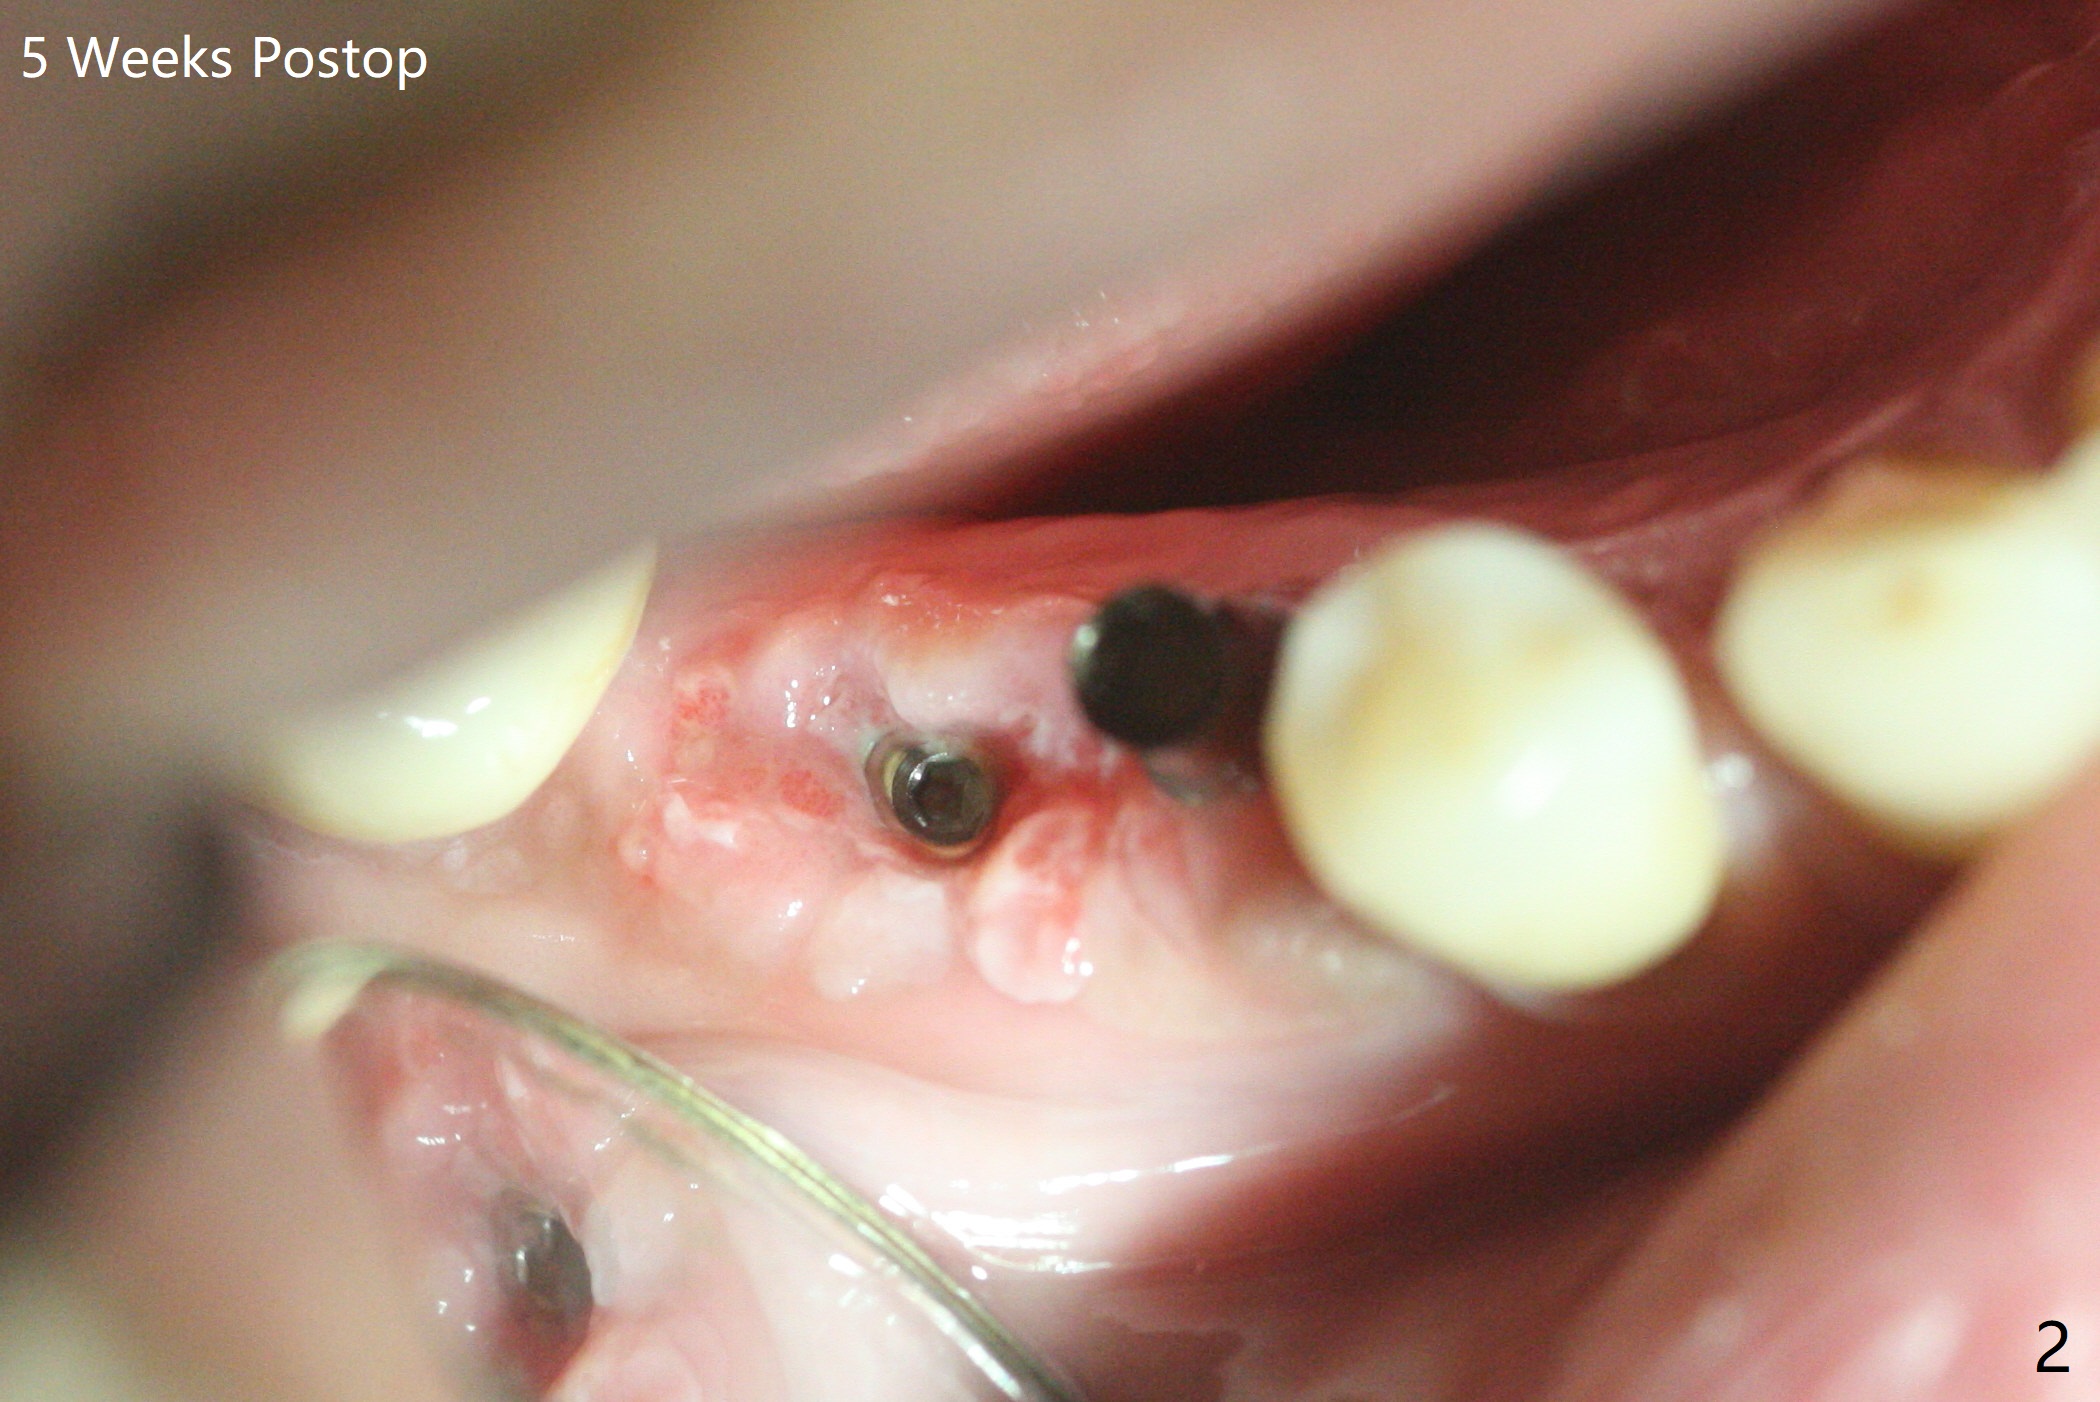

右下5,6植体植入后,取下导板,发现两者都植入不够深,放回导板,5植体植入深点(35Ncm),但是6植体与植牙工具通过导板接不上,正好取出导板,徒手旋紧,不幸的是植体往近中移位(图一:空箭头,远离中隔(S)),稳定性好像降低,不适合即刻修复,放置愈合螺帽后,大量植入粘性骨粉,包括进入7近中(短箭头,事先需要往上分离龈乳头),覆盖PRF膜,PGA缝线,利用5基台,固定树脂敷料。术后5个星期,撤除树脂敷料,虽然愈合螺帽暴露,周围牙龈健康,并含有骨粉(图二)。术后两个月植体基本被覆盖(图三),术后3.5个月植体完全覆盖,切开前根尖片显示植体平台与牙槽嵴平齐(图四),术中证实。5基台好像没有就位(图四(可能拍摄角度不佳)),将基台平面从远中旋转至颊侧,就位仿佛改善(图五)。术后四个月6放置基台后(图六),制作连体5,6牙冠,垫高(打开咬合),近中衬里,推4,关闭3,4之间间隙(图三)。6植体远中第一个螺纹好像暴露。